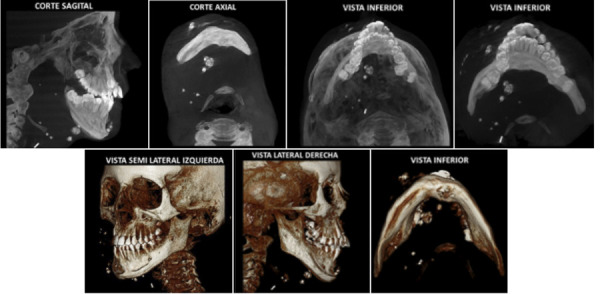

Vascular alterations or disorders of the blood and / or lymphatic vessels have their own characteristics, the identification of calcifications being a correct parameter to be able to make a proper diagnosis. The objective of the study was to describe the radiographic characteristics of the phleboliths, and whether they represent a challenge for diagnosis. according to the literature reviewed in the Medline (PubMed) database, Scielo, Google Scholar and some specialized journals. Phleboliths were found to have very particular radiographic characteristics, with concentric radiolucent and radiopaque images that resemble rings. However, not all the presentations are similar, this makes the diagnosis misleading with other calcifications in this region, such as sialoliths where their appearance is usually similar. Furthermore, there is the relationship with vascular anomalies and hemangiomas. finally, the evidence points to very specific characteristics of this lesion, and it is necessary to individualize each case, due to the differences that exist from one patient to another.